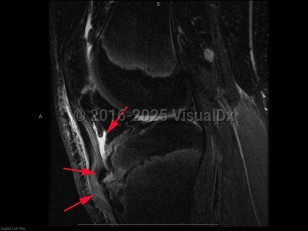

Causes / typical injury mechanism: Osgood-Schlatter disease (OS), also known as juvenile osteochondrosis of the tibial tubercle, is a disorder involving inflammation, pain, and swelling of the tibial tuberosity. It is most common in young adolescents, particularly those regularly involved in athletics. OS typically occurs soon after a growth spurt. Symptoms last for 12-18 months, often resolving spontaneously with the closure of the physeal plate of the tibia, although there is a small subset of patients who experience pain after skeletal maturation.

Pathophysiology: The underlying pathophysiology of OS is poorly understood. Its association with sports participation has led to the hypothesis that it is related to repeated small injuries to the developing knee associated with traction from the patellar tendon.